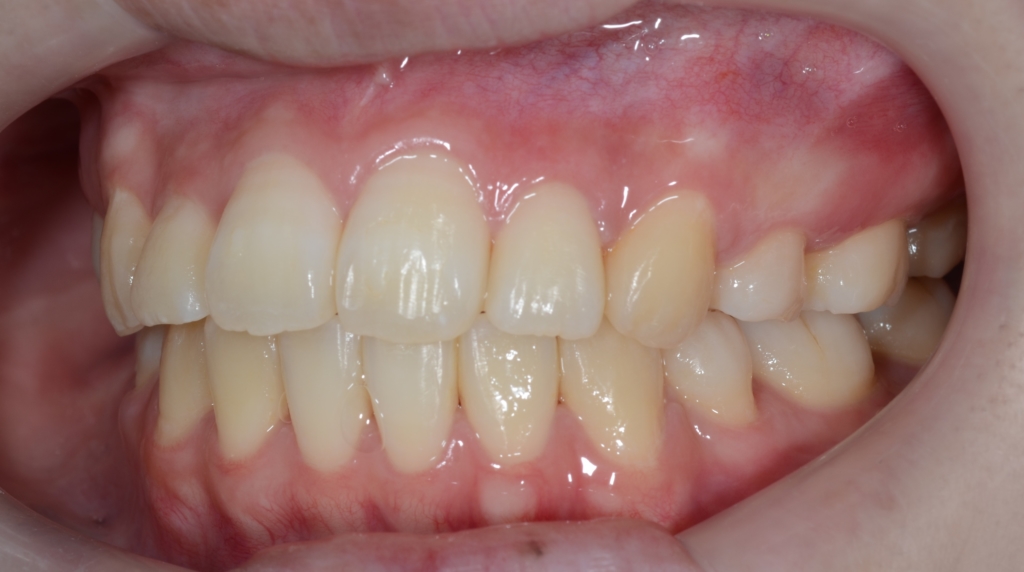

【After】

矯正治療の結果、狙い通りに口元をスッキリさせることが出来ました。

お口を閉じるのにも「力」が要らなくなり、楽に閉じれるようになった!と喜んでもらいました。

また、Eラインに収めることは出来ませんでしたが、患者さん的には引っ込み過ぎるは嫌なので、元々あった口元の突出感も無くなり、このくらいがちょうど良い!とのこと。